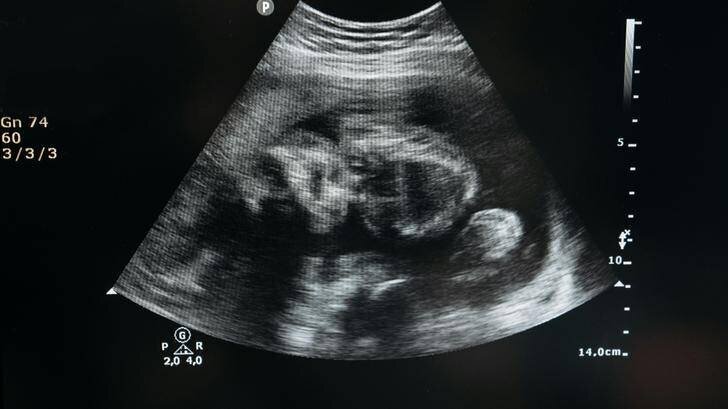

Les futurs parents ont appris le sexe de leur deuxième enfant lors d’une « gender reveal party » organisée avec un gâteau dont l’intérieur a révélé une couleur rose. Joacquia Sherman avait prévu l’événement en petit comité, mais la nouvelle a fait venir des membres de leur famille de différents États, ainsi que des caméras qui ont filmé la scène.